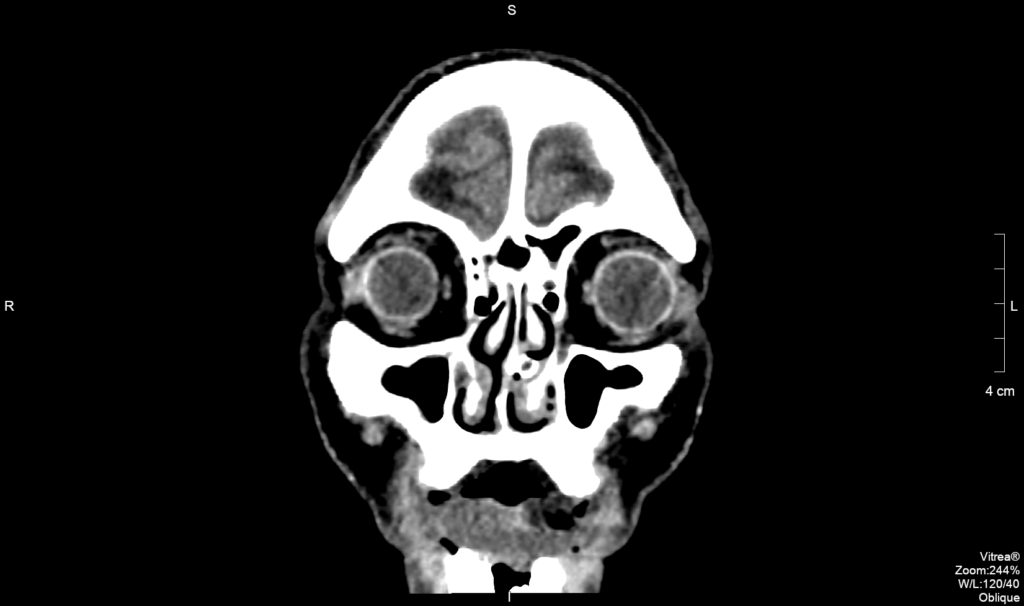

A tomografia computadorizada das órbitas é um exame de diagnóstico por imagem de alta qualidade, que permite a avaliação desta região de maneira anatômica, sendo ela um exame que serve não só para auxiliar o médico no estudo de diversas patologias (doenças) como também para avaliar as respostas aos tratamentos. Em algumas situações, é solicitado o uso de contraste iodado – via endovenosa –, para uma visualização mais detalhada da área desejada.

A órbita é uma cavidade do esqueleto da face onde se “encaixa o olho”. Anatomicamente tem uma forma de pirâmide, permitindo acomodar o bulbo do olho, os músculos que permitem a movimentação do olho, os nervos, os vasos sanguíneos e o aparelho lacrimal (para a produção de lágrimas).